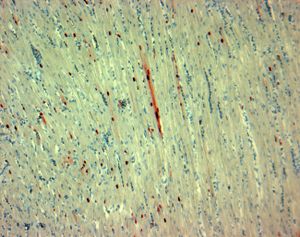

CSIRO ScienceImage 322 Avian influenza in the heart of a turkey.jpg

فيروس الإنفلونزا أ H7N3 هو أحد أنماط فيروس الإنفلونزا أ، سبب عدد من فاشيات إنفلونزا لدى الطيور.